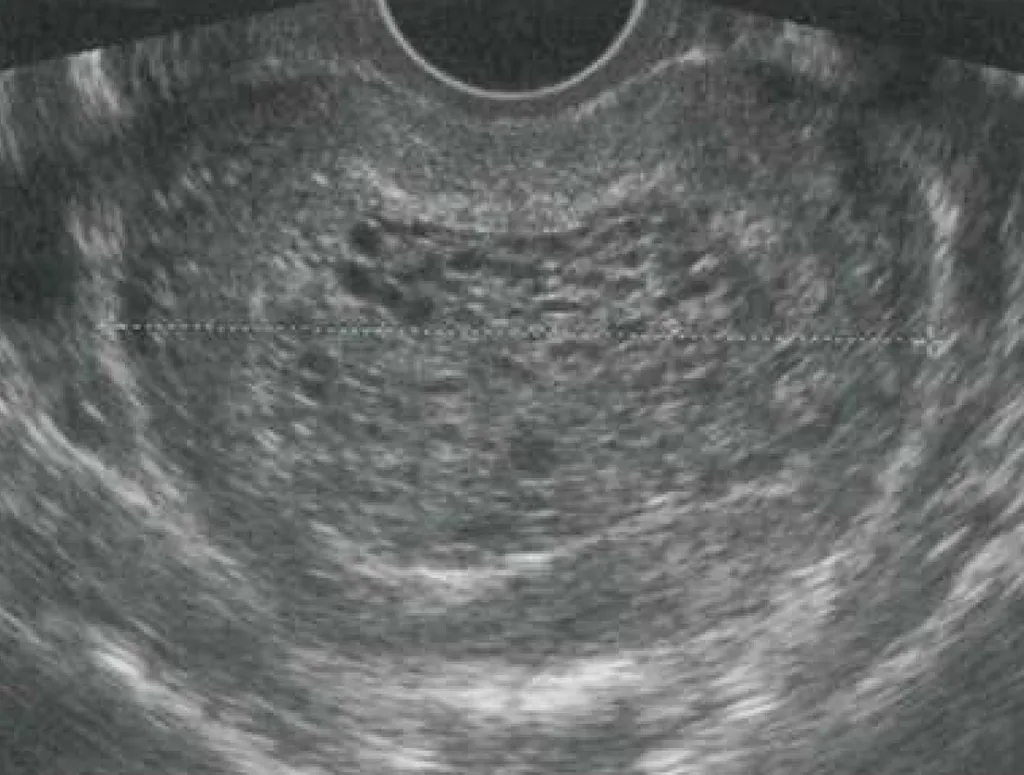

【113-1 醫學(六) 第29題】25 歲女性因最近一天內出現大量陰道出血而來到急診就診,這位女性自述:最近一週出現嚴重噁心感、最後一次月經開始日為 6 週前、自行驗孕尿液懷孕試驗呈陽性反應,到急診時,其血壓為 140/90 mmHg、心跳每分鐘 120 下,身體理學檢查發現其子宮大小約為懷孕 12 週、子宮頸長度正常且子宮頸口關閉未開,抽血檢驗發現血清β-人類絨毛膜刺激激素(β-subunit human chorionic gonadotropin, β-hCG)值為 400,000 mIU/mL,骨盆腔超音波檢查發現如圖所示:在子宮腔內充滿雜回音性的(mixed echogenic)組織且伴隨很多的低回音性的囊狀間隙(anechoic cystic spaces)、似暴風雪狀(snowstorm appearance)、看不到羊膜囊或胎兒發育。下列何者為最正確的診斷?

詳解

破題關鍵

這題的解題核心在於辨識超音波影像中「暴風雪狀」的特徵,並結合臨床上異常高的β-hCG值和子宮大小與預期不符的線索。圖片中子宮腔內充滿了不均勻的雜回音性組織,其中散佈著許多小小的低回音性囊狀間隙,這正是妊娠滋養層細胞疾病(特別是葡萄胎)的典型超音波表現。

選項拆解